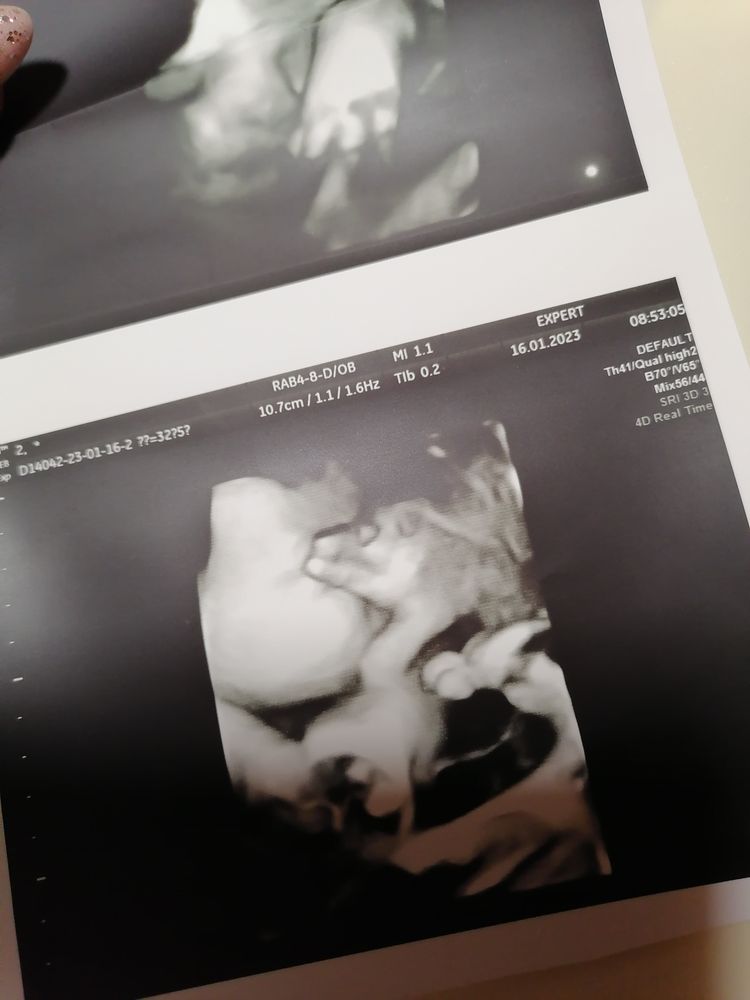

Наши 33-34 недели💙

💙В 32,5нед сходила на узи. Наш сладкий пирожок 45см и 2221кг,сказал что крупненький парень, мы только рады))) Щёчки наел, обвития нет и сказал не будет, кокушки опустились. Шов 2,5-2,7мм тонковат, но доносить должна. До 28 февраля сказал доходить и можно сдаваться. Я если честно надеюсь родить к этому времени. Гиня насчитала ПДР на 6 марта, по мес 8 марта.

На фото муж в детстве и сын в 24 нед, как думаете похож?)